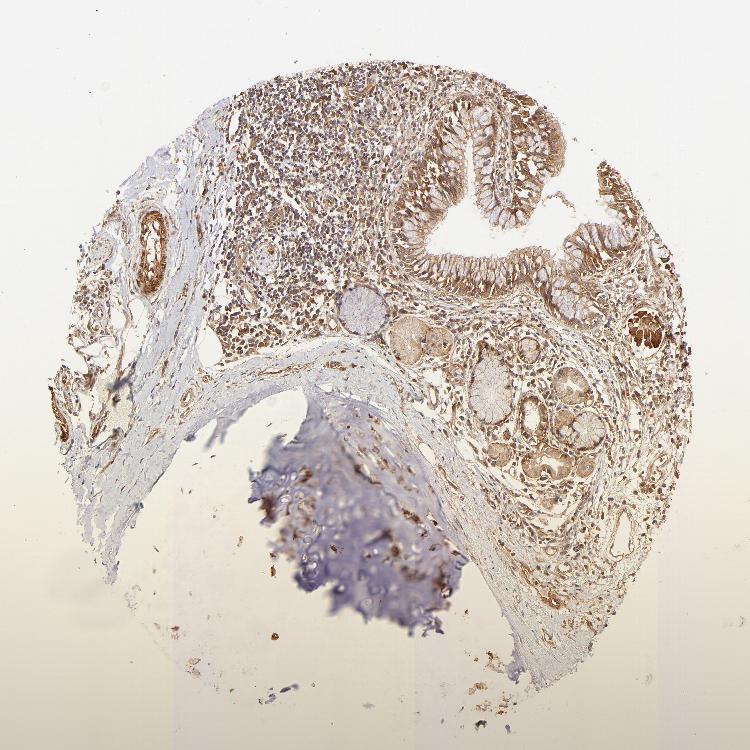

SOFT TISSUE 2 - Antibody stainingi

Antibody staining in the annotated cell types in the current human tissue is reported as not detected, low, medium, or high, based on conventional immunohistochemistry profiling in selected tissues. This score is based on the combination of the staining intensity and fraction of stained cells.

Each image is clickable and will lead to virtual microscopy that enables deeper exploration of all samples and also displays staining intensity scores, fraction scores and subcellular localization as well as patient and tissue information for each sample.

Antibody HPA059297Antibody HPA069003Antibody CAB003434

Fibroblasts Not detectedNot detectedMedium

Peripheral nerve -Not detectedMedium